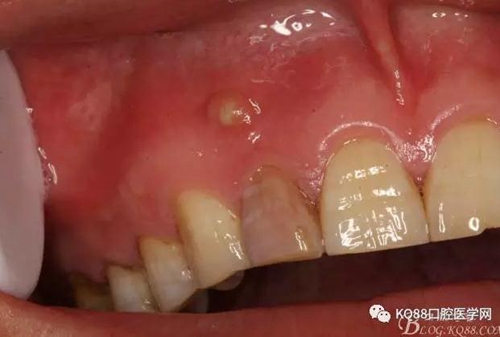

患者、張xx、前牙唇側(cè)牙齦反復溢膿數(shù)年?,F(xiàn)病史:患者數(shù)年前、無誘因發(fā)現(xiàn)前牙牙齦腫痛溢膿,曾在當?shù)鼐驮\,治療經(jīng)過不詳,治療效果不佳,唇側(cè)溢膿現(xiàn)象為消除,遂來我院就診。??茩z查:21舌側(cè)有開髓孔、根管開放,牙冠成灰褐色。唇側(cè)粘膜有一膿瘺。捫診溢膿。12無松動。x光檢查:12根尖區(qū)橢圓形陰影,界限清楚。診斷:12根尖周炎伴發(fā)根尖囊腫。治療:12行根管治療。一個月后。唇側(cè)膿瘺未消失。建議根管外科手術(shù),患者同意手術(shù)。簽手術(shù)知情同意書。

一個月后患者復查: 唇側(cè)觀:11根尖區(qū)粘膜有一膿瘺,捫診溢膿,牙冠成灰褐色。根管治療無法治愈根尖病變,建議根管外科治療,患者同意手術(shù)。